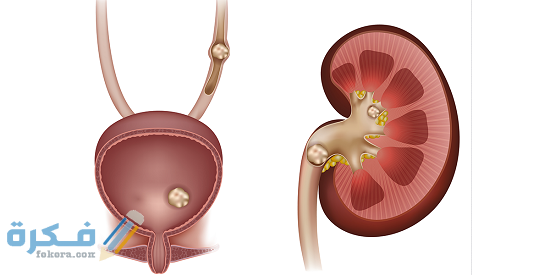

- تتكون حصوات الكلى في الكلى او في اى جزء من المسالك البولية ابتداء من الكلى وحتى المثانة .

- يستطيع الجسم التخلص التلقائي من حصوات الكلى الصغيرة التي يتراوح حجمها من 5-10 ملم بنسبة 90 % على الأقل .

- تبدأ أحجام حصوات الكلى الكبيرة من حجم 10 ملم إلى ما فوق .